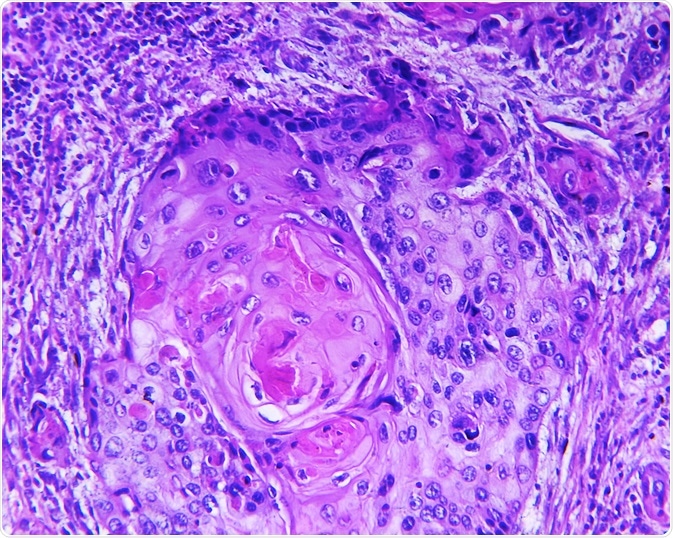

squamous cell carcinomaSquamous cell carcinoma of a human. Image Credit: Designua / Shutterstock.com

Image Credit: Designua / Shutterstock.comDiagram of squamous cell carcinoma. Image Credit: Designua / Shutterstock.com